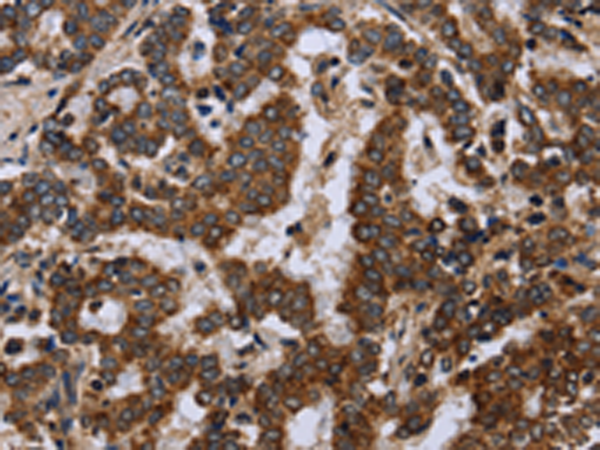

分类: 科研抗体货号: P01447别名: HDL; 11-DH; HSD11; HSD11B; HSD11L; CORTRD2; SDR26C1; 11-beta-HSD1应用: IHC反应种属: Human